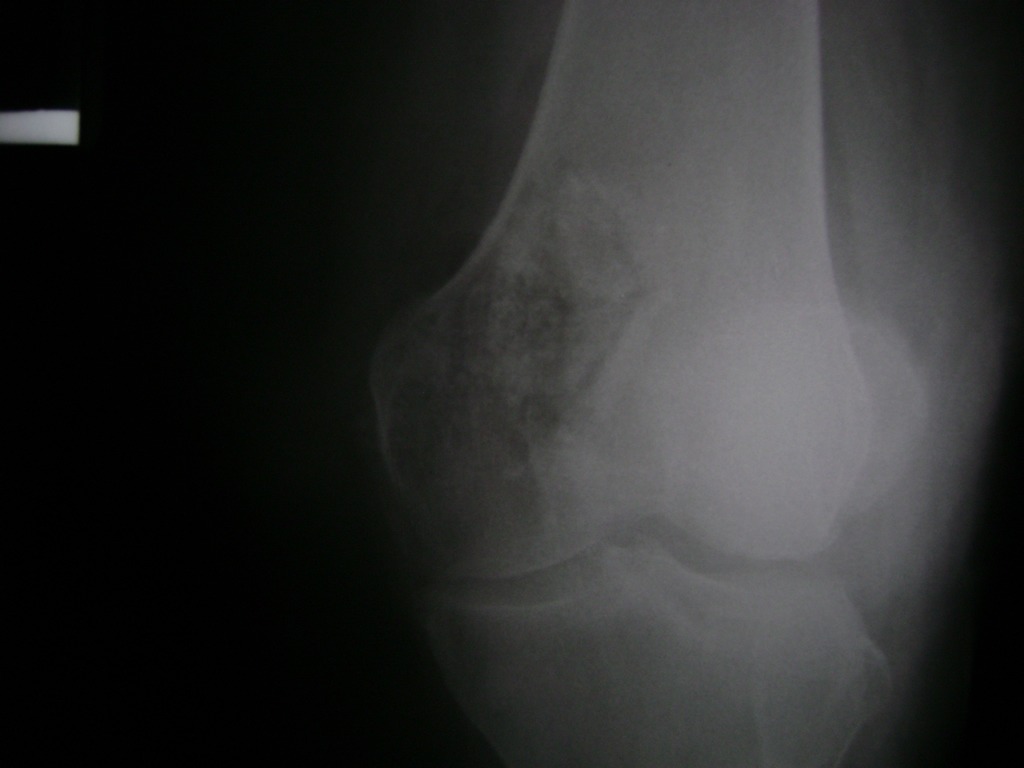

La artroscopia de rodilla es un cirugía en el cual la estructura interna de la articulación es examinada ya sea para realizar un diagnostico o para realizar un tratamiento, este procedimiento se realiza utilizando un instrumento parecido a un pequeño tubo llamado artroscopio.